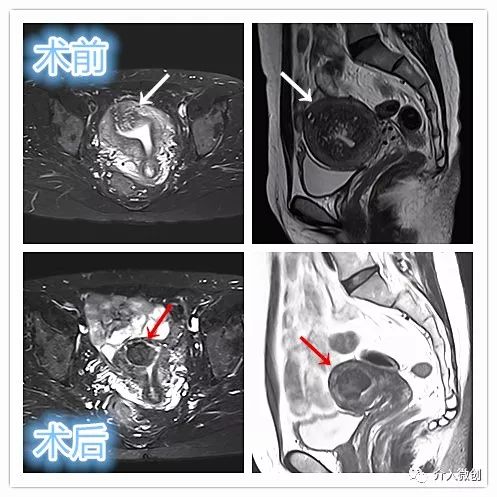

术前子宫MRI提示宫腔明显增大,诊断为子宫腺肌瘤

术后4个月复查,子宫明显缩小,腺肌瘤明显坏死吸收